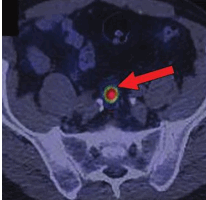

![]() | ![]() |

| Рисунок 4. Накопление радиофармпрепарата 68 Ga-DOTA-TATE пораженными лимфатическими узлами у пациента с НЭО прямой кишки. | |